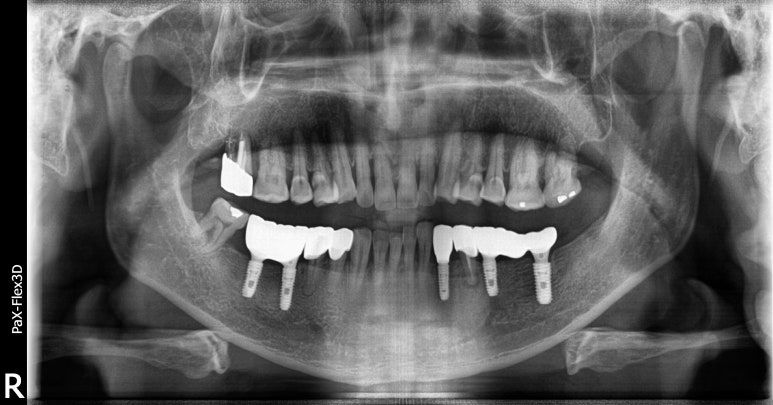

68세 남성

보험임플란트

(전) 2021-11-05 (후) 2022-08-18

만 65세 이상으로 국가에서 금액을 일부 지원하는 보험임플란트를 진행하신 환자분입니다.

치아가 상당 부분 결손되어 있어 생활하시는데 불편함이 많으셨을텐데, 임플란트 시술 후 씹는 즐거움을 되찾을 수 있었습니다.

상실된 치아를 방치하게 되면 치아가 조금씩 이동해 치아 배열이 망가지고 임플란트 식립이 어려워질 수도 있습니다.

따라서 빠르게 치과에 방문하셔서 치료받으시는 것이 가장 좋습니다.